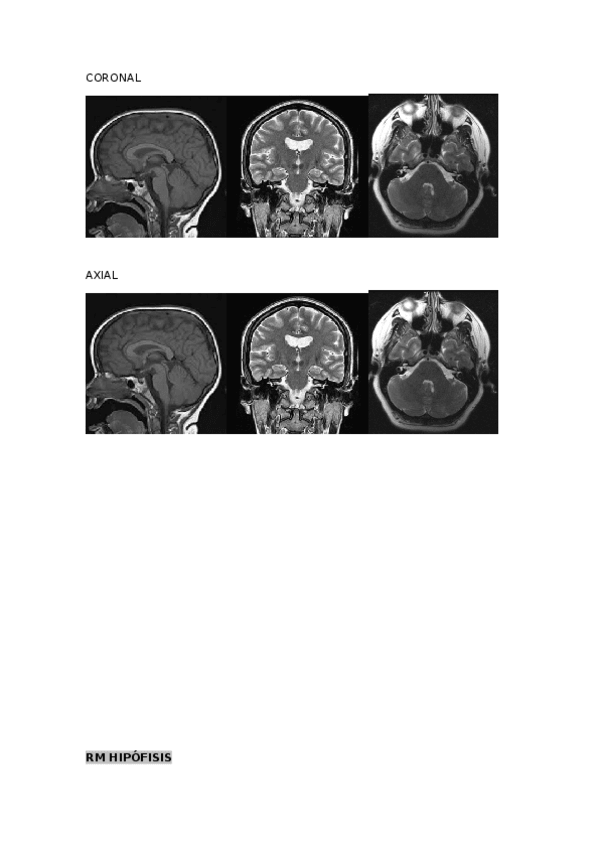

He publicado nuevos apuntes de Técnicas de Imagen por Resonancia Magnética: ACTIVIDADES-RM-1.docx

word